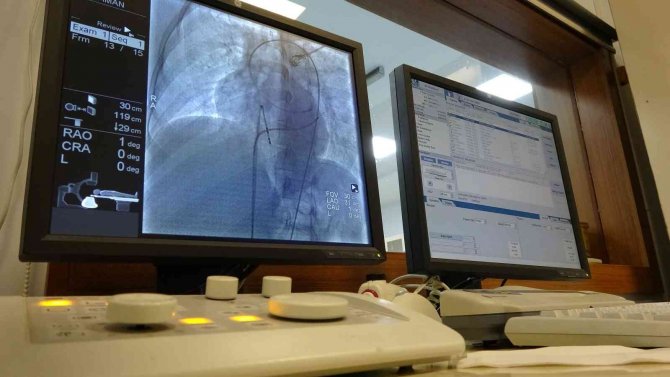

SBÜ Van Eğitim ve Araştırma Hastanesi'nde Kardiyoloji Uzmanı Dr. Gürkan İmre tarafından kasık veya el bileği yerine başparmak bölgesinden anjiyo yöntemi uygulanmaya başlandı. Türkiye'de nadir olarak el başparmak bölgesinden yapılan anjiyografi yöntemi, hem hasta hem de doktor açısından büyük konfor sağlıyor. Yapılan bu uygulamayla, kasık veya el bileği yönteminde yaşanan şiddetli ağrı, kanama ve damar büzüşmesi gibi sorunlarla karşılaşılmıyor. Ayrıca bu yöntemle yapılan anjiyo sayesinde hastalar 2 saat gibi kısa sürede taburcu olabiliyor.

Kalbin damarlarını görüntülemek için "koroner anjiyo" denilen kalp anjiyosu yaptıklarını dile getiren Kardiyoloji Uzmanı Dr. Gürkan İmre ise "Bunu daha önceki dönemlerde sürekli kasıktan yapıyorduk. Son 5-10 yıllık süreçtir tüm Türkiye'de ve dünyada el bileğinden yapılmaya başlamıştık. Ancak el bileğinden yaptığımız zaman özellikle genç ve kilolu kadınlarda "spazma" denilen damar büzüşmesi ve şiddetli ağrı olabiliyordu. Yeni trendimiz başparmak sırtından kalp anjiyosu yöntemidir. Bu şekilde herhangi bir spazm olayı olmuyor. Hastayı 2 saat içerisinde taburcu edebiliyoruz. Aynı uygulamayla stent de takabiliyoruz. Bu son derece konforlu ve kanama riski daha azdır. Hem hasta hem de doktor için çok uygun bir yöntemdir. Hastanemizde başparmak sırtından anjiyolara başladık. Hastalarımıza bu uygulamayı tavsiye ediyoruz" diye konuştu.

Türkiye'de sadece birkaç merkezde bu uygulamanın yapıldığını hatırlatan İmre, hastanede şu ana kadar 5'ten fazla hastaya bu yöntemle anjiyo yapıldığını kaydetti.